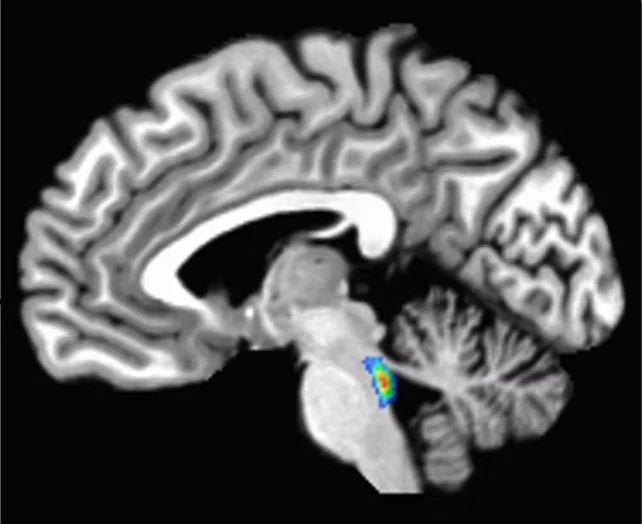

Situated within the brainstem, the most caudal portion of the brain, lies the locus coeruleus. Its nomenclature, translating to “blue spot,” derives from the presence of a pigment called neuromelanin, which is synthesized by its constituent cells.

The locus coeruleus, a region colloquially known as the ‘blue spot,’ is anatomically situated within the brainstem. (Elizabeth Riley/CC BY-SA 4.0)

The initial stages of these cerebral alterations involve the aberrant aggregation of a protein known as tau. This abnormal tau begins accumulating in a diminutive, deep-seated brain region responsible for regulating sleep, attention, and wakefulness – the locus coeruleus. Subsequently, this abnormal tau disseminates throughout the wider brain.

The formation of tau tangles does not inherently indicate the presence of Alzheimer’s disease; indeed, this phenomenon occurs to varying extents in nearly all individuals. However, given that these pathological changes originate in the locus coeruleus, some neuroscientists, including myself, regard this area as a critical early indicator, akin to a harbinger for the development of Alzheimer’s disease.